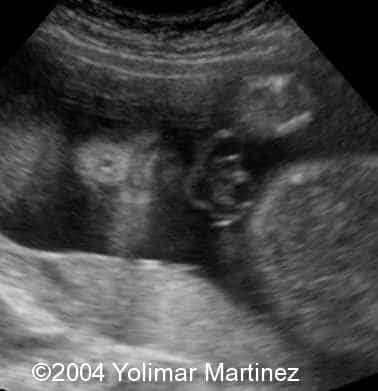

Microophthalmia and hypotelorism

Imagen 38